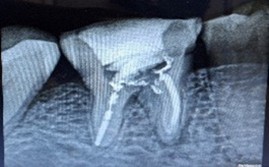

A 51-year-old woman presented with a 15-day history of persistent pain in the right mandibular posterior region. Her dental record showed multiple failed restoration attempts and an incomplete root canal on tooth 46, yet her symptoms persisted. Clinical examination and intraoral periapical radiography revealed furcation involvement, a large periapical radiolucency, and a perforation in the pulp chamber floor.

Despite a guarded prognosis for tooth survival, we performed thorough canal disinfection and placed Metapex as an intracanal medicament for four weeks. The patient reported no inter-appointment discomfort. At the subsequent visit, radiographs confirmed complete resolution of the periapical lesion, and root canal obturation was successfully completed.

Figure 1: Pre operative IOPA wrt 46 showing incomplete root canal treatment, with furcation involvement, a large periapical lesion and perforation of pulp chamber floor.

Figure 1: Pre operative IOPA wrt 46 showing incomplete root canal treatment, with furcation involvement, a large periapical lesion and perforation of pulp chamber floor. Figure 2: Metapex placement after thorough canal disinfection.